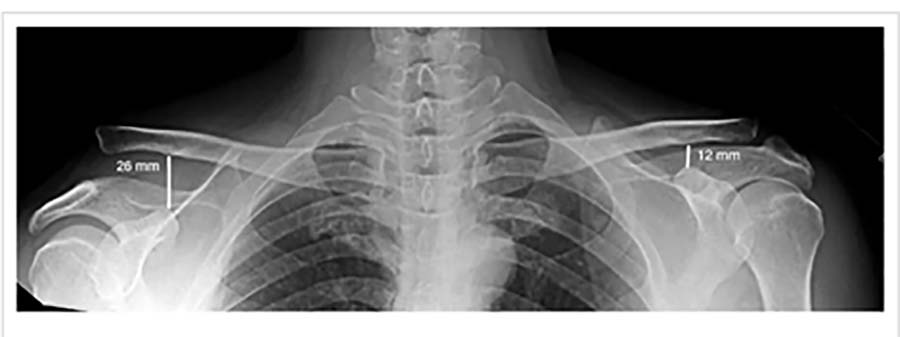

FRATURA DA CLAVICULAR

A clavícula é o osso responsável em ligar o esqueleto axial ao membro superior. A fratura deste osso é comum, e acomete principalmente homens jovens com idade abaixo de 20 anos, após uma queda sobre o ombro. A maioria (80-85%) das fraturas da clavícula ocorrem no terço médio. Geralmente apresenta inchaço, com arroxeado local de pele e geralmente com a movimentação se ouve pequenos estalos Essas fraturas, quando com pouco desvio, podem ser tratadas conservadoramente com imobilização. Em casos de cirurgia existem 2 opções principais: colocação de placa e parafusos ou uma haste intramedular.